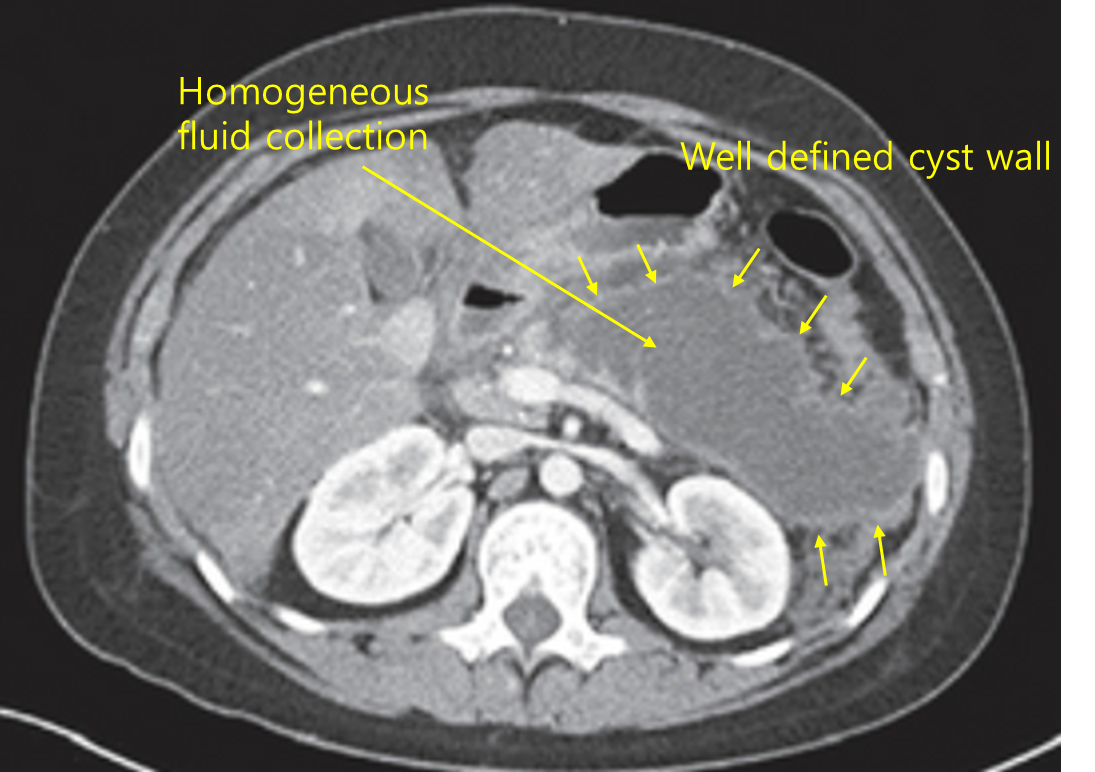

Img | CT: 얇은 피막으로 둘러싸인 저음영의 낭종 |

Imp: 췌장 거짓낭종(pancreatic pseudocyst)

• 음주력과 혈액검사 상 amylase, lipase 상승, 증상의 재발 등으로부터 재발성 급성 췌장염을 의심할 수 있고, 복부 CT 소견으로부터 급성 췌장염의 합병증으로 발생한 췌장 거짓낭종을 진단할 수 있다.

췌장가성낭종 | • CT: 경계가 명확하고 homogeneous한 저음영 fluid • 치료: 무증상시 경과관찰, 유증상시 내시경적/경피적/수술적 배액술 |